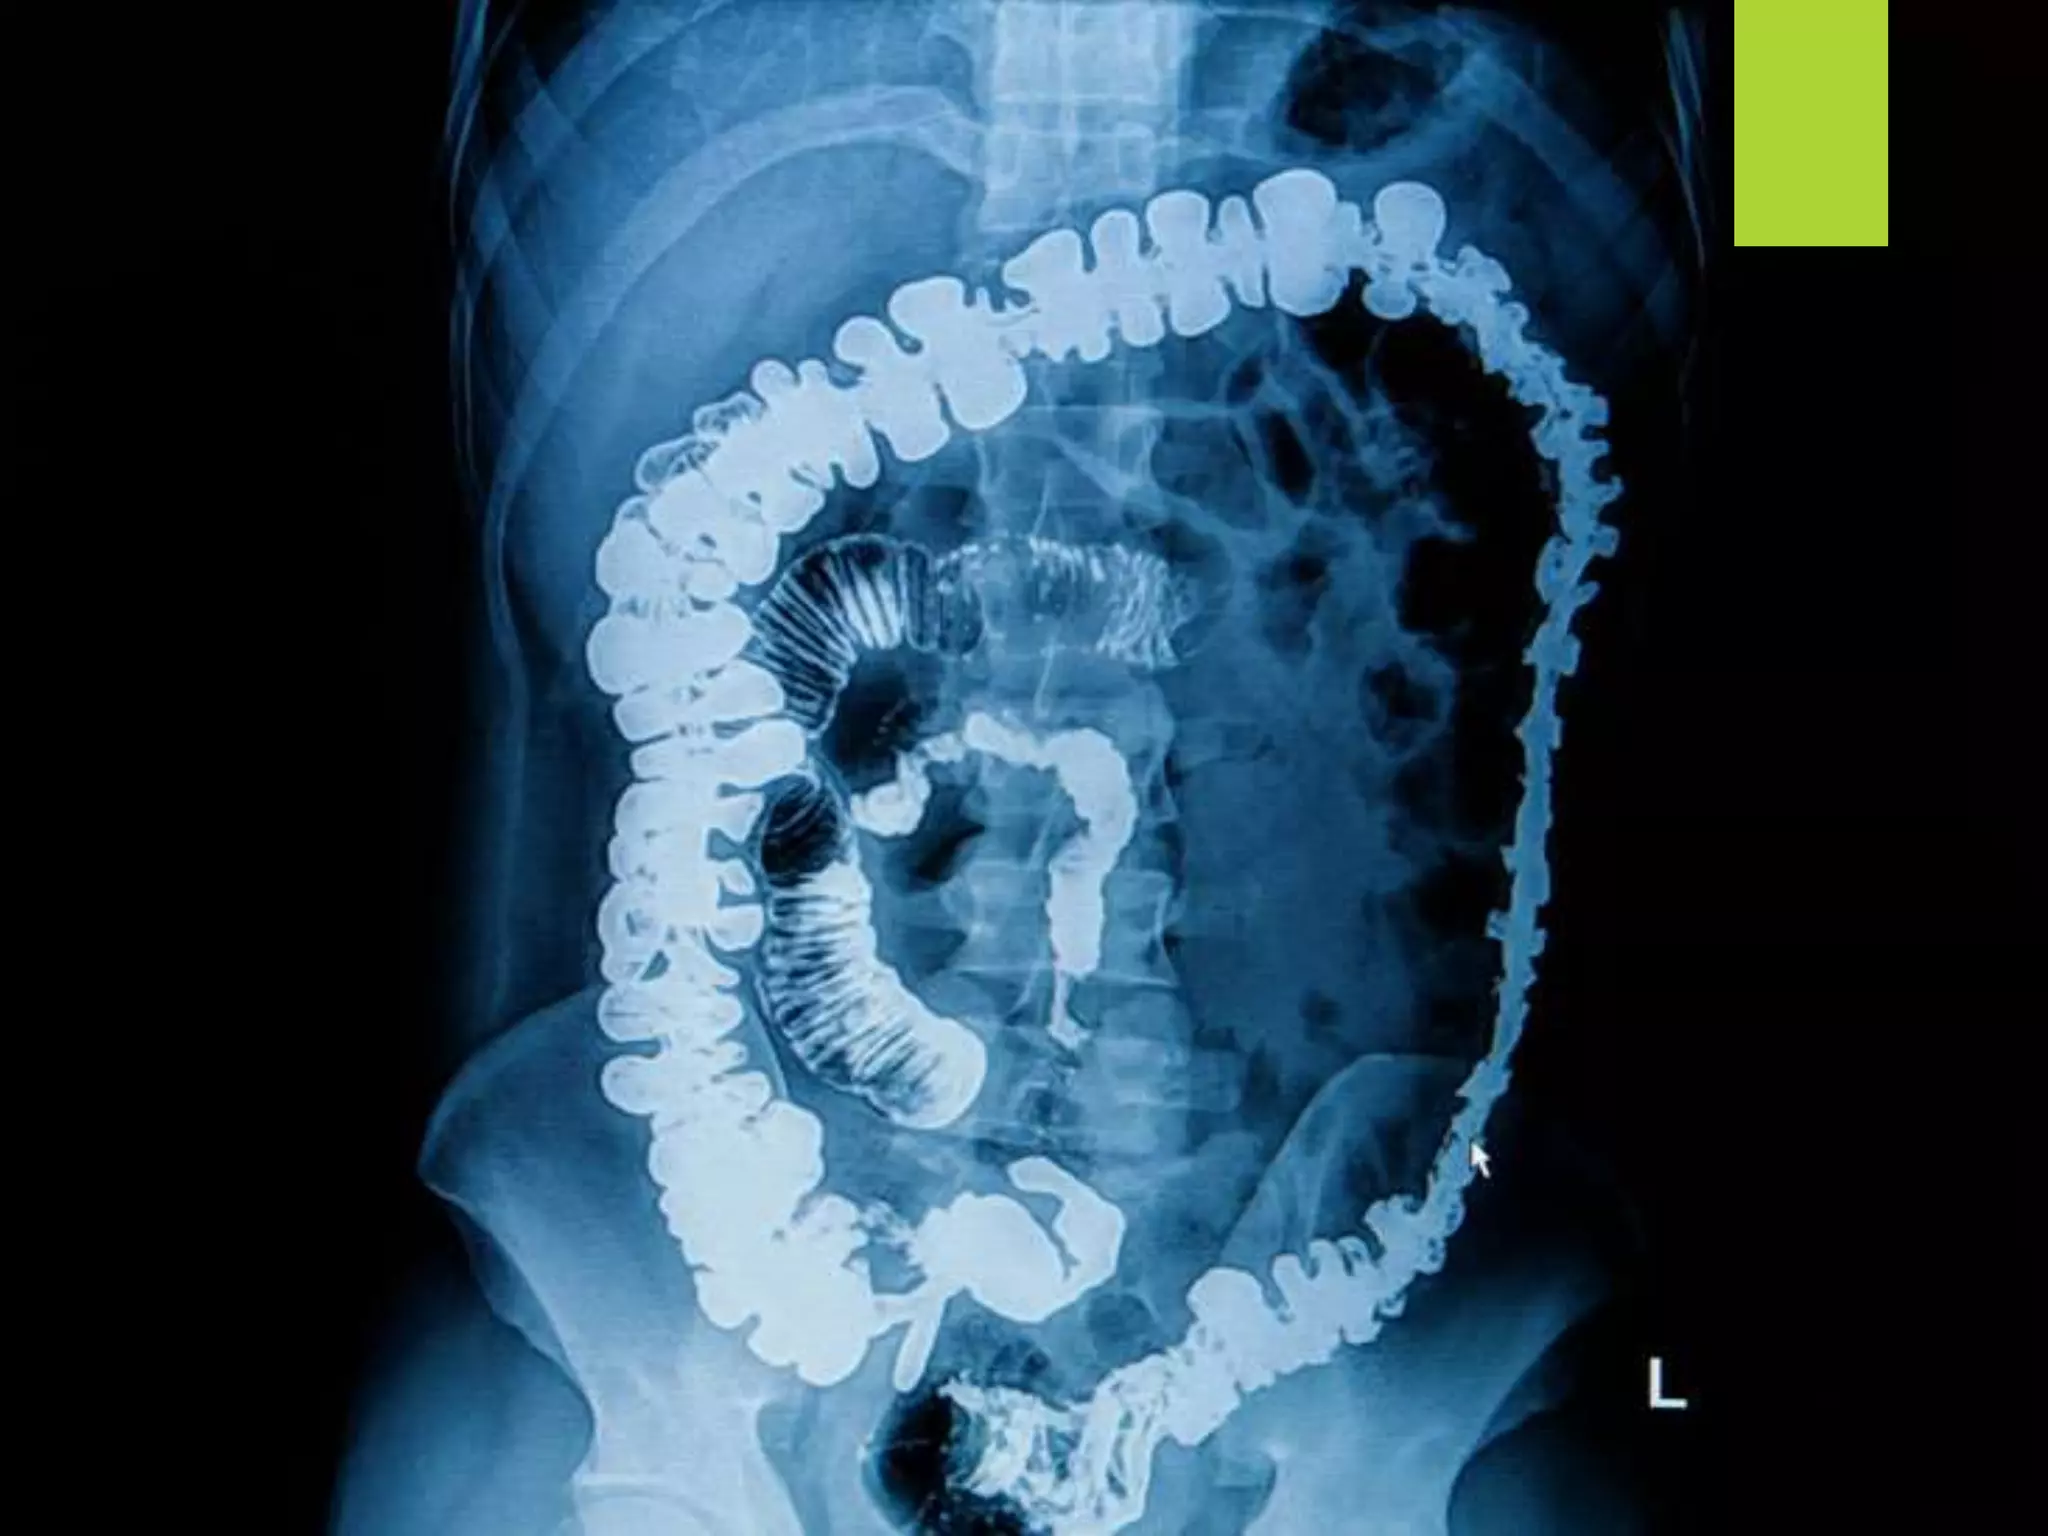

 Barium sulfate is used for the X-ray examination of

the GIT (‘barium-meal’).

Physical properties  Itis a heavy, white, tasteless, odorless powder and insoluble in water.  Barium sulfate is used for the X-ray examination of the GIT (‘barium-meal’).